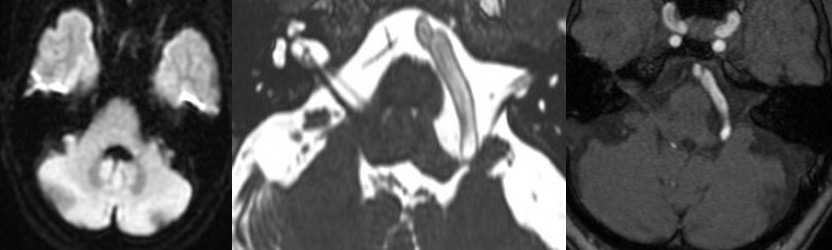

VAが脳神経を引き伸ばしており、M-TEPを用いて延髄虚血をモニタリングし、Wallenbergの発生を予防しました。少しの小脳牽引で迷走神経反射が生じたり、ABRが低下したりしたが、少しずつやっていくことでうまく徐圧できました。特に後遺症なく、痙攣は消失しました。